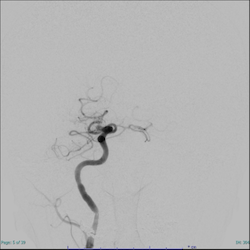

図. 管撮影:治療前(左)は血管が途絶しているが、治療後(右)では途絶していたところから血管が描出されるようになった

一方で、時間がたって場合には再開通させても末梢の血流が改善しないNo-reflow現象が知られています。